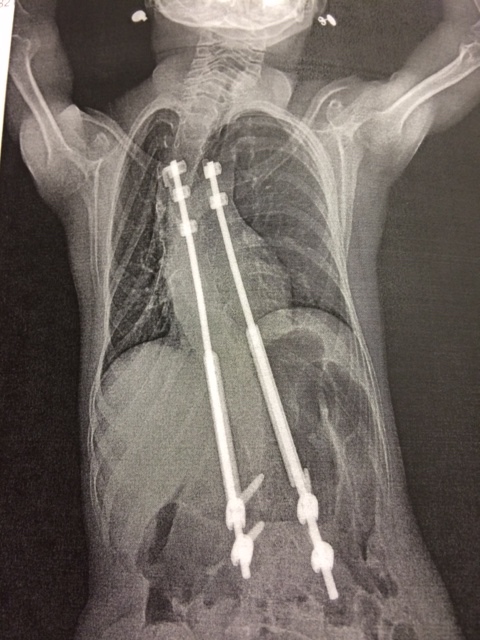

One day when Mrs. Wesson was getting her ready for her bath she noticed that one of Abby’s shoulder blades was prominent and the other was almost non-existent. An appointment was made and upon examination her pediatrician stated that Abby had developed scoliosis. They were sent to an orthopedic doctor for further evaluation. She was diagnosed with extreme scoliosis and kyphoscoliosis. A custom brace was made that she had to wear 23 hours a day. She had enough time to take a bath without it but that was it. She wore a brace for the next 3 years but her back continued to get worse. It eventually got so bad that it was starting to restrict her lungs and heart. Her doctor did not want to perform surgery but the Wessons were not satisfied with the treatment because it simply wasn’t working. They went to South Carolina to the Shriner’s Hospital hoping that might be able to help her. Sadly, what she needed done was something that they did not do. They asked her pediatrician for recommendations and she said she would see what she could come up with. She called one day with some information about a doctor in Atlanta Georgia that she thought was just what Abby needed. It was a long way but they decided to go because they wanted the best for their little girl. It was the right choice. They ended up loving her new doctor and he immediately looked at her and said that something had to be done because her heart and lungs could not handle much more pressure. He placed one VEPTR rod and 6 months later placed a second one.

Twice a year since then she underwent surgery to adjust the rods and then last year had to have them removed and replaced with larger rods. At age 5 she underwent surgery to remove ½ of one of her vocal cords, which helped open her airway enough to remove the tracheostomy tube just prior to her 6th birthday. At about age 7 her feeding tube was also removed. In the process she underwent a few minor surgeries such as tonsils and adenoids. In 2012 she was diagnosed with dyslexia, an issue she struggles with daily but having the knowledge of it gave the Wessons the tools they needed to find different ways for her to learn. She was once a student that struggled with everything but as of this year she has had all A’s and B’s. Her parents are so proud of her.

Abby still has a long road ahead. She will have to undergo surgery twice a year until the time comes to remove the growing rods and fuse all of her vertebrae together. She will be ready for that process within the next couple of years and the surgery will be quite a large one. She continues to battle with her weight. She has not gained weight in 3 years and is currently at a whopping 48 pounds and is 12 years old. She is overall a very small girl. This past year she grew out of toddler size shoes and was so excited. Abby deals with pain in her back and sides often but has a very high tolerance for pain. She is not a complainer and when she does you know she is hurting.